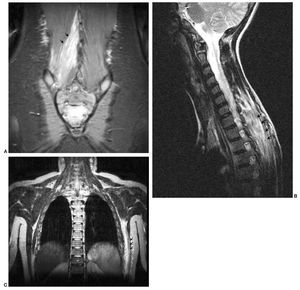

La piomiositis puede afectar a un músculo (fig. 2A) o a un grupo muscular2,4,12,15. Los músculos más comúnmente afectados son los del muslo y la región de la cadera: glúteos, aductores, obturador y psoas ilíaco (fig. 2B). La afectación preferente a este nivel hace que muchas veces el diagnóstico diferencial de la piomiositis sea extenso y se realice con artritis séptica, sinovitis transitoria, osteomielitis y/o procesos intraabdominales (apendicitis)16,17. En nuestra serie se evidencia esta predominancia, encontrando sólo tres casos de localización atípica, que afectaban a los músculos dorsal ancho, musculatura paravertebral cervical y lumbar (fig. 3).

Fig. 2. (A) Afectación de un único músculo. Resonancia magnética (RM) en secuencia coronal STIR mostrando una área de elevada señal que afecta al músculo obturador externo derecho. (B) RM en secuencia axial STIR mostrando la afectación de los diferentes grupos musculares de la pelvis, obturador interno, externo, pectíneo, psoas y glúteo menor.

Fig. 3. (A) Localización atípica de la piomiositis. La secuencia coronal STIR revela la afectación de la musculatura lumbar paraespinal derecha. (B) Localización atípica de la piomiositis. Secuencia sagital STIR que muestra la hiperseñal de la musculatura paraespinal dorsal, romboides y erectores de la columna. (C) Localización atípica de la piomiositis. Secuencia coronal STIR con hiperseñal del músculo dorsal ancho.